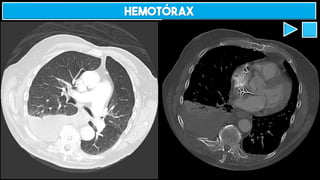

HEMOTÓRAX

HEMOPNEUMOTÓRAX